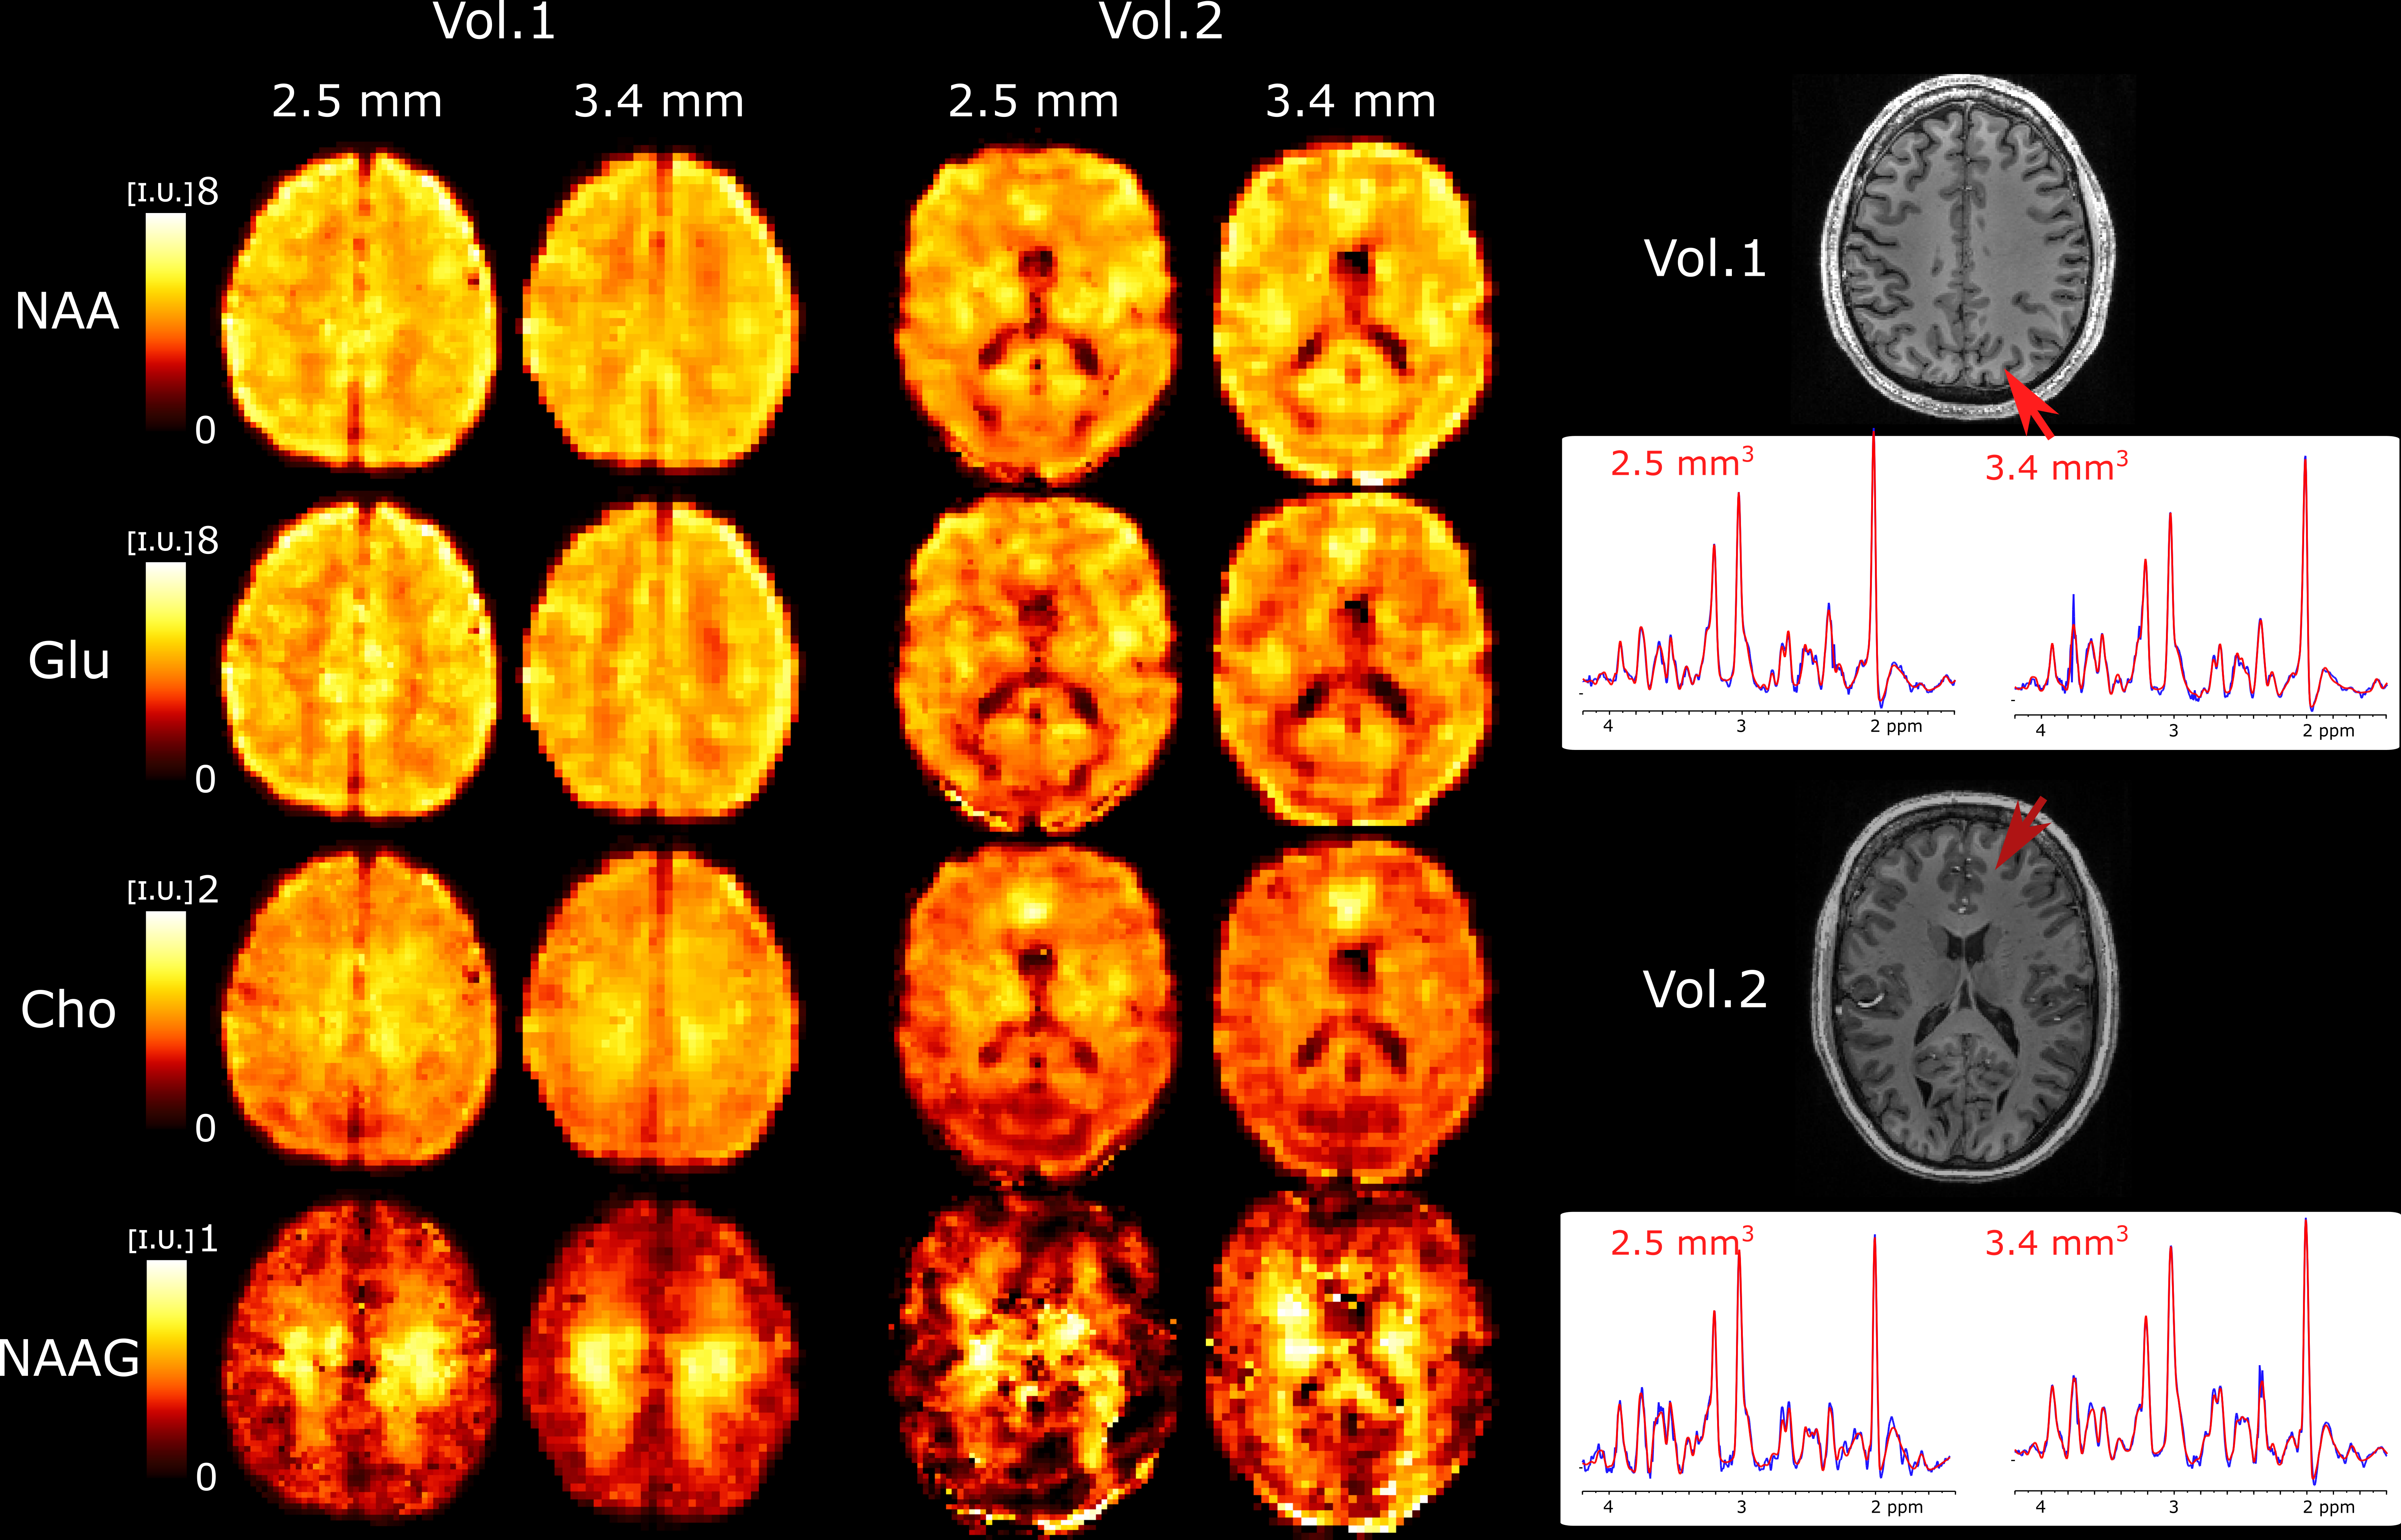

We further explored the performance of 3D ECCENTRIC FID-MRSI for ultra-high resolution metabolic imaging in several healthy volunteers. Based on the high SNR of the 3.4 mm data we expected that smaller voxels at higher resolution will still provide sufficient SNR for metabolite imaging. Fig.6 shows metabolic images obtained using 3D ECCENTRIC FID-MRSI with isotropic voxel size of 2.5 mm in two healthy volunteers.

Refer to caption

Figure 6: Ultra-high resolution metabolic imaging acquired with 3D ECCENTRIC FID-MRSI at 2.52.52.5 mm isotropic voxel size (AF=4𝐴𝐹4AF=4, TA=10min:26s:10𝑚𝑖𝑛26𝑠10min:26s) in two healthy volunteers. The ultra-high resolution metabolic imaging is compared to 3D ECCENTRIC FID-MRSI at the typical voxel size of 3.43.43.4 mm isotropic (AF=2𝐴𝐹2AF=2, TA=9min:20s:9𝑚𝑖𝑛20𝑠9min:20s). Right, two spectra from both spatial resolution and corresponding to the red arrow location are shown. The blue line represents the MRSI data and the red line is the fit performed by LCModel.

To achieve a feasible scan time, we used CS with AF=4𝐴𝐹4AF=4. We demonstrated at the beginning of our work that AF=4𝐴𝐹4AF=4 provides metabolic maps that are similar to those obtained through fully sampled 3D ECCENTRIC FID-MRSI. The AF=4𝐴𝐹4AF=4 acceleration enabled the acquisition of 3D ECCENTRIC FID-MRSI at 2.52.52.5 mm isotropic resolution in 10min:26s. For comparison we also acquired the typical 3D ECCENTRIC FID-MRSI at 3.43.43.4 mm isotropic with AF=2𝐴𝐹2AF=2 acceleration in 9min:20s. As readily apparent by visual inspection, the metabolic maps at higher spatial resolution provide sharper delineation of the brain structure. No compromise is visible for signal-to-noise, contrast-to noise or other data quality metric at ultra-high resolution compared to typical resolution. We note that the acquisition time of 3D ECCENTRIC FID-MRSI at 2.52.52.5 mm with AF=4𝐴𝐹4AF=4 is only slightly longer (111 min) than at 3.43.43.4 mm with AF=2𝐴𝐹2AF=2. However, for the same acceleration factor the acquisition time of 3D ECCENTRIC FID-MRSI at 3.43.43.4 mm is 2.22.22.2 times faster than at 2.52.52.5 mm.